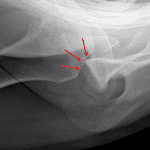

- Anterior shoulder dislocation with an acute Hill-Sachs impaction fracture

- Anterior shoulder dislocation with Hill-Sachs fracture

Anterior shoulder dislocation with an acute Hill-Sachs impaction fracture. No definite bony Bankart lesion; however recommend attention on postreduction views.

- Hill-Sachs

- Occurs along the posterolateral humeral head where the humeral head impacts on the glenoid

- Best seen on internal rotation views

- Reverse Hill-Sachs from posterior dislocation -> impaction fracture of the inferomedial humeral head, which results in a “trough” sign on radiographs